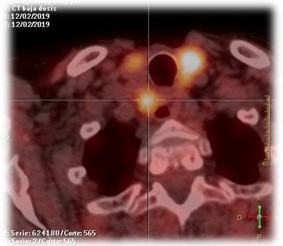

Surgical excision was considered. Fine-needle aspiration (FNA) of the paraesophageal node revealed mature lymphoid cells with low cellularity. Based on clinical and imaging findings, left lymph node dissection was performed. Histopathology confirmed parathyroid carcinoma in infraclavicular and retrocarotid lymph nodes (Figure 2).

Figure 2: (A) Parathyroid carcinoma implant. (B) Positive immunohistochemical study.

PC remains a diagnostic challenge. Clinical suspicion should be raised by suggestive findings such as calcium >14 mg/dL, cervical lesions >3 cm, renal (nephrolithiasis, nephrocalcinosis) and skeletal abnormalities (osteoporosis, vertebral fractures). Definitive diagnosis relies on histopathological evaluation (Figure 2).